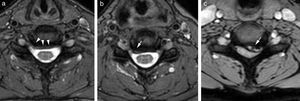

Para el estudio axial, las diferentes secuencias de pulso tienen unas ventajas y unos inconvenientes. Con las secuencias eco de gradiente se diferencia mejor entre el componente óseo osteofitario y el disco, y permite diferenciar entre la sustancia gris y la sustancia blanca; las secuencias 3D FSE con pulso Drive (mantienen el efecto mielográfico T2 con un TR corto) valoran las emergencias radiculares con mayor resolución sin el artefacto de flujo de LCR. Las técnicas sensibles al agua, T2 con supresión química de la grasa o STIR permitirán visualizar mejor el incremento del agua extracelular, el edema, y son importantes para diferenciar el edema intraóseo debido al contenido graso de la médula ósea y de las partes blandas (fig. 2)5,7–9.

Hernia se define como un desplazamiento focalizado de material discal por fuera de los límites del espacio intervertebral; dependiendo de la morfología, se considera hernia protruida o protrusión cuando tiene una base ancha, y hernia extruida o extrusión cuando el diámetro anteroposterior es mayor que el diámetro transversal en el plano axial o cuando en el plano sagital excede la altura del espacio intervertebral. En función de la localización del disco se clasificará en central, centrolateral o paralateral, lateral, foraminal o extraforaminal (figs. 8 y 9).

Dado el solapamiento de los cambios degenerativos en la población sintomática y asintomática, estos se deben interpretar con precaución24,25. La presencia de disminución de la IS de los discos, abombamientos o pequeñas protrusiones que incluso improntan sobre la columna de LCR son frecuentes en la población asintomática. Se asocian más a sintomatología la presencia de hernias extruidas y la estenosis de canal22,24,25.

Estenosis foraminalLa RM es el método aceptado para valorar lesiones medulares; sin embargo, su resolución es menor en la valoración del componente óseo. La estenosis foraminal puede estar causada por osteofitos o herniaciones discales laterales. La precisión para valorar la causa de estrechamiento foraminal se ha visto que es menor con RM que con TCMD, aunque los planos en orientación oblicua pueden ser de utilidad. Se debe al tamaño del agujero de conjunción, al grosor de corte, a osteofitos que ocultan hernias discales y a la intensidad de señal similar del anillo fibroso, la dura y el hueso32,33.